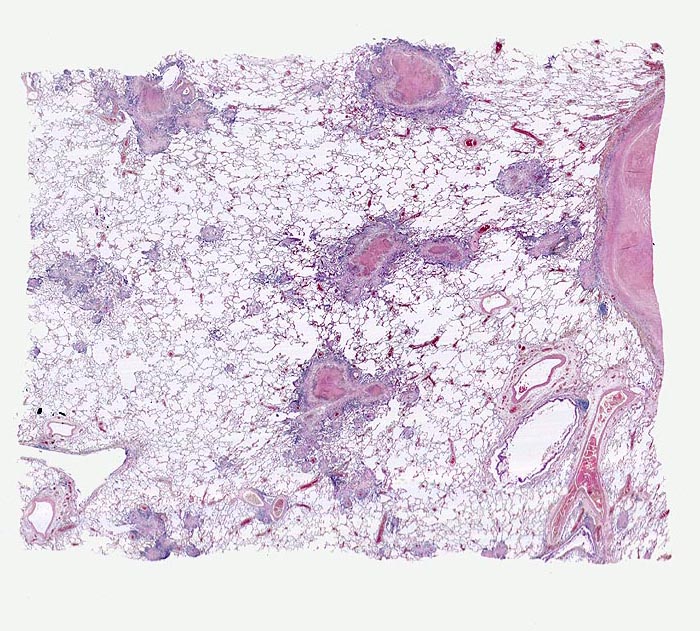

An Tuberkulose erkranken nur ca. 10% der exponierten und infizierten Personen in der Regel innerhalb von zwei Jahren nach Infektion. Eine Tuberkuloseerkrankung (Fortschreiten oder Reaktivierung der Infektion) tritt vor allem im Kleinkindesalter und bei beeinträchtigter Funktion des Immunsystems auf (HIV Infektion, immunsuppressive Therapien, Diabetes mellitus, Raucher, Unterernährung...). Selten verläuft die Primärinfektion progredient mit Entwicklung einer meist einseitigen Ausbreitung der Herde mit Frühkavernenbildung, verkäsender Pneumonie und oft einer hämatogenen Frühstreuung. Die progressive Lymphknotentuberkulose des Primärkomplexes ist der häufigste Ausgangspunkt der lympho-hämatogenen Streuung in der Primärperiode. Die isolierte Organtuberkulose der Lunge wird Lungenphthise genannt. Dabei handelt es sich meist um eine Exazerbation alter, vorwiegend apikaler hämatogener vorübergehend zur Ruhe gekommener Streuherde bei verminderter Resistenzlage oder seltener um eine kontinuierliche phthisische Entwicklung im Rahmen einer hämatogenen Streuung. Eine hämatogene Streuung kann ausgehen von primären oder postprimären, pulmonalen oder extrapulmonalen Herden. Sie kann bei verminderter Resistenzlage jederzeit vorkommen. Das Spektrum reicht von einzelnen kleinen Streuherden bis zur miliaren Aussaat (> 2865) (> 3680) mit bakterienreichen areaktiven käsigen Herden bei der Tuberkulosepsis

Das morphologische Bild ist äusserst variabel. Je nach Abwehrlage, Art und Geschwindigkeit der Ausbreitung entstehen unterschiedlich grosse, teils geschichtete Herde mit unterschiedlichem Grad an Epitheloidzellreaktion, zentraler Nekrose bzw. Vernarbung. Rein produktive Granulome ohne Nekrosen sind Zeichen guter Abwehrlage. Der Begriff Verkäsung bezieht sich auf den makroskopischen Aspekt von Nekrosen, der an Frischkäse erinnert. Exsudative nekrotisierende Granulome entstehen bevorzugt bei schlechter Abwehrlage. In späteren Stadien der Lungentuberkulose unterscheidet man produktive Phthisen mit azinös nodösen Gruppen von bronchogen entstandenen gering verkäsenden Streuherden (Präparat), zirrhotische Phthisen mit gering verkäsenden stark vernarbenden Herden und exsudative Phthisen bei schlechter Abwehrlage. Bei letzterer steht die Verkäsung im Vordergrund. Die bakterienreichen Herde entstehen teils hämatogen, teils bronchogen. Verkäsende Herde sind Ausgangspunkt für die Kavernenbildung. Kavernen stellen die wichtigste Quelle für die bronchogene Streuung dar.

• Tuberkulöse Herde ausgehend von vollständig oder partiell entzündlich zerstörten Bronchiolen in unmittelbarer Nachbarschaft von Arterien.